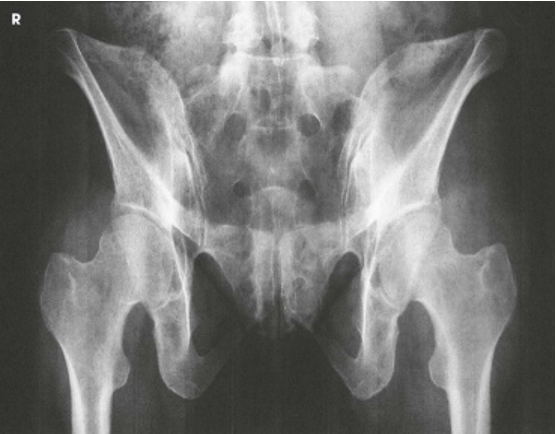

AP Oblique Projection; Proximal Femora and Femoral Necks; Modified Cleaves Method (CR & SS)

Perpendicular to enter the patient’s midsagittal plane at the level 1 inch (2.5 cm) superior to the pubic symphysis. For the unilateral position, direct the central ray to the femoral neck

The bilateral image shows an AP oblique projection of the femoral heads, necks, and trochanteric areas onto one radiograph for comparison

AP Oblique Projection; Proximal Femora and Femoral Necks; Modified Cleaves Method (Eval Criteria)

• Evidence of proper collimation

• No rotation of the pelvis, as demonstrated by a symmetric appearance

• Acetabulum, femoral head, and femoral neck

• Lesser trochanter on the medial side of the femur

• Femoral neck without superimposition by the greater trochanter; excess abduction causes the greater trochanter to obstruct the neck.

• Femoral axes extended from the hip bones at equal angles

• Soft tissue and bony trabecular detail